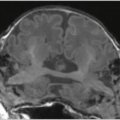

Перед вами — уникальное МРТ сразу двух человек. Это МРТ Кристы и Татьяны Хогарт. Они — краниопаги, сросшиеся черепами сиамские близнецы. Но их случай — совсем особый случай.